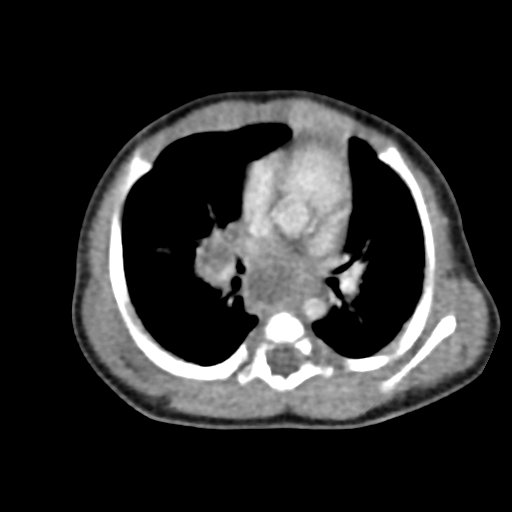

Infant tuberculosis (TB) is a rare but potentially deadly infection and difficult to diagnose, especially in infants who may present with non-specific symptoms. Here, we report a case of an United States-born term infant with community-acquired miliary TB and no confirmed TB exposure history. The patient initially presented with respiratory distress at seven weeks of life with chest radiograph showing a right lower lobe (RLL) infiltrate. After failing multiple courses of treatment for community-acquired pneumonia and developing growth faltering, the patient had imaging findings suggestive of TB infection with CNS involvement. The diagnosis of TB was confirmed by QuantiFERON and purified protein derivative (PPD). In infants who fail conventional treatment for bacterial pneumonia, the differential should be broadened to consider alternative etiologies. Additionally, brain imaging should be performed in cases of disseminated TB despite negative cerebrospinal fluid (CSF) studies since these patients are at high risk of central nervous system (CNS) involvement.